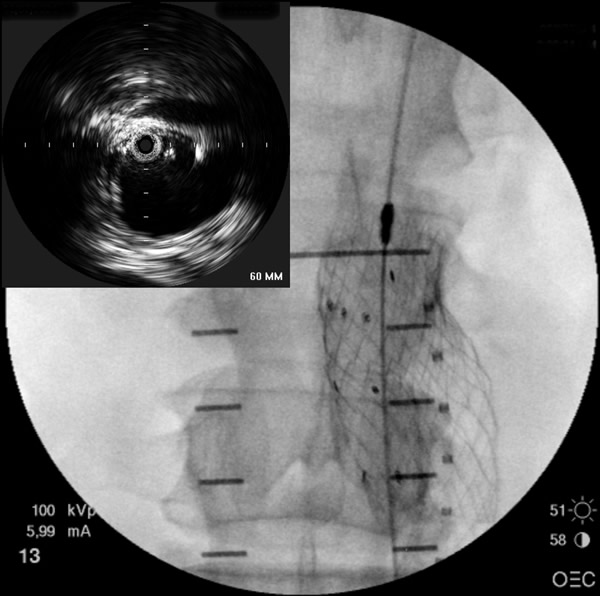

- Initially a 9F introducer sheath is inserted over the primary access guidewire in the more agreeable femoral artery. If there is a concern about aortic rupture, a 12F sheath may be used in order to accommodate large diameter occlusion balloon. A 5F Bern or multipurpose catheter is introduced to facilitate guidewire exchange to a stiff wire (such as the Meier wire or Amplatz). This wire will straighten tortuosity of the access vessel and improve tracking capability of the introduced catheters and devices. An intravascular ultrasound (IVUS) catheter is advanced over the stiff guidewire for inspection of the abdominal aorta. The use of IVUS allows the surgeon to interrogate the entire abdominal aorta and the iliac vessels and to map out (on the fluoroscopic screen) the renal and internal iliac arteries without the use of contrast/fluoroscopy. On the contralateral side, a 5F pigtail catheter to be used for angiography is introduced over the initial guidewire.

- The contralateral limb of the endograft will be introduced over another stiff guidewire inserted from the contralateral femoral artery. Deployment of the contralateral limb of the endograft is most often accomplished through retrograde cannulation of the contralateral limb gate of the main trunk, but other methods can be employed if difficulty is encountered. Cannulation of the contralateral limb gate from a retrograde femoral artery approach is commonly achieved by first using a maneuverable guidewire and steerable catheter. Antegrade or crossover cannulation involves passing a guidewire from the ipsilateral limb to the contralateral limb gate of the endograft, which can be accomplished with a curved catheter (such as SOS-Omni). The wire may be retrieved on the contralateral limb using a snare device. Cannulation can also be achieved using an approach from the brachial/radial artery. To confirm that the guidewire is inside the endograft and not between the graft and vessel wall, a pigtail or other curved catheter can be inserted over the guidewire. The ability to rotate the catheter freely without resistance provides a “relative” assurance that the guidewire is within the endograft (rather than between the endograft and the aortic wall). Also, anteroposterior and oblique fluoroscopic views may help confirm the location of the wire. However, while these “tricks” work well in a majority of cases, they may fool the surgeon in some instances. The only accurate way to confirm the location of the wire within the contralateral gate is to advance the IVUS catheter and visualize the contralateral gate.

- After the deployment of the contralateral iliac limb (Figure 4), the surgeon will evaluate the need for further iliac limb extenders or aortic cuffs. It is important to cover the entire length between the lowest renal artery and the internal iliac artery. The stent grafts are subsequently ballooned as suggested by the IFU. An IVUS interrogation of the entire stent graft and surrounding aortic branches is performed. This will detect any circumferential stent mal-apposition to the proximal or distal landing zone that may lead to endoleak. A completion angiogram is performed to confirm lack of gross endoleak (Figure 5, Video 1, , “Completion angiogram” confirms the patency of both renal arteries and lack of proximal endoleak (type Ia).) However a single aortogram may miss endoleak due to projection overlap. A bi-plane aortogram is more reliable in excluding any significant procedural endoleak.